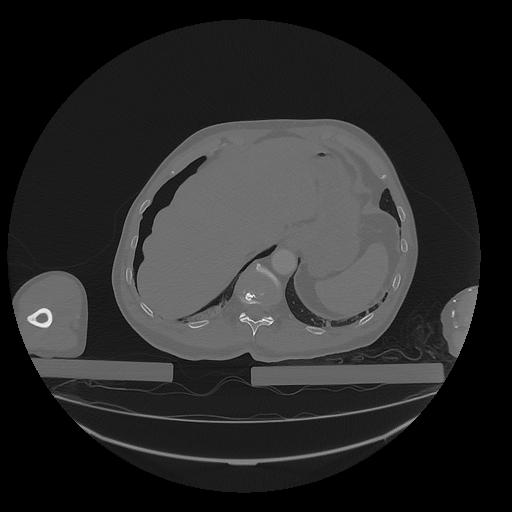

31 PULMON,CE,Vol,1.0,PULMON,,